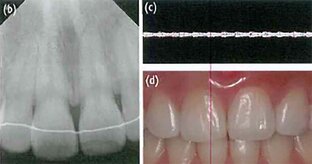

Использование ультразвуковой допплерографии для определения жизнеспособности потемневшего зуба после травматического повреждения: перспектив

Когда зуб обесцвечивается и не реагирует на холодовой тест или электроодонтодиагностику (ЭОД) после травматического повреждения, его диагностика может быть затруднена из-за отсутствия надлежащих методов диагностики для оценки его жизнеспособности. В данных отчетах о применении мы надеемся продемонстрировать, что ультразвуковая допплерография может успешно использоваться для оценки жизнеспособности зуба после травмы и поможет сократить применение ненужных эндодонтических методов лечения. Во всех трех...